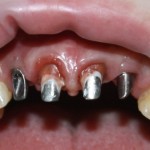

Около трёх лет назад к нам в клинику обратилась пациентка Мария, на момент обращения ей было 45 лет. Её беспокоила ситуация с передними резцами:

В ходе беседы она рассказала, что лечит эти зубы всю сознательную жизнь — их депульпировали («удалили нерв») из-за последствий травмы еще в школьном возрасте, и после этого каждые несколько лет (а то и чаще) ей приходилось перелечивать каналы, менять коронки, вкладки и т. д.

В результате, зубы приобрели очень уж нездоровый вид (см. фото выше). Вдобавок, всё усугубилось существенным снижением качества жизни — коронки и вкладки из зубов постоянно выпадают, десна вокруг них кровоточит при чистке…. Кроме того, Марию не покидает ощущение того, что эти зубы могут просто вывалиться в самый неподходящий момент. Именно это заставило её обратиться в нашу клинику.

Визуальный осмотр:

Подвижность зубов (или коронок) II-III степени косвенно свидетельствует о разрушении периодонтальных связок и стенок лунок зубов. Подвижность является следствием хронического воспаления, когда окружающие зуб ткани остаются без питания и деградируют — и в совокупности это может существенно осложнить сохранение эстетических параметров окружающих имплантат тканей. Степень риска — высокая.